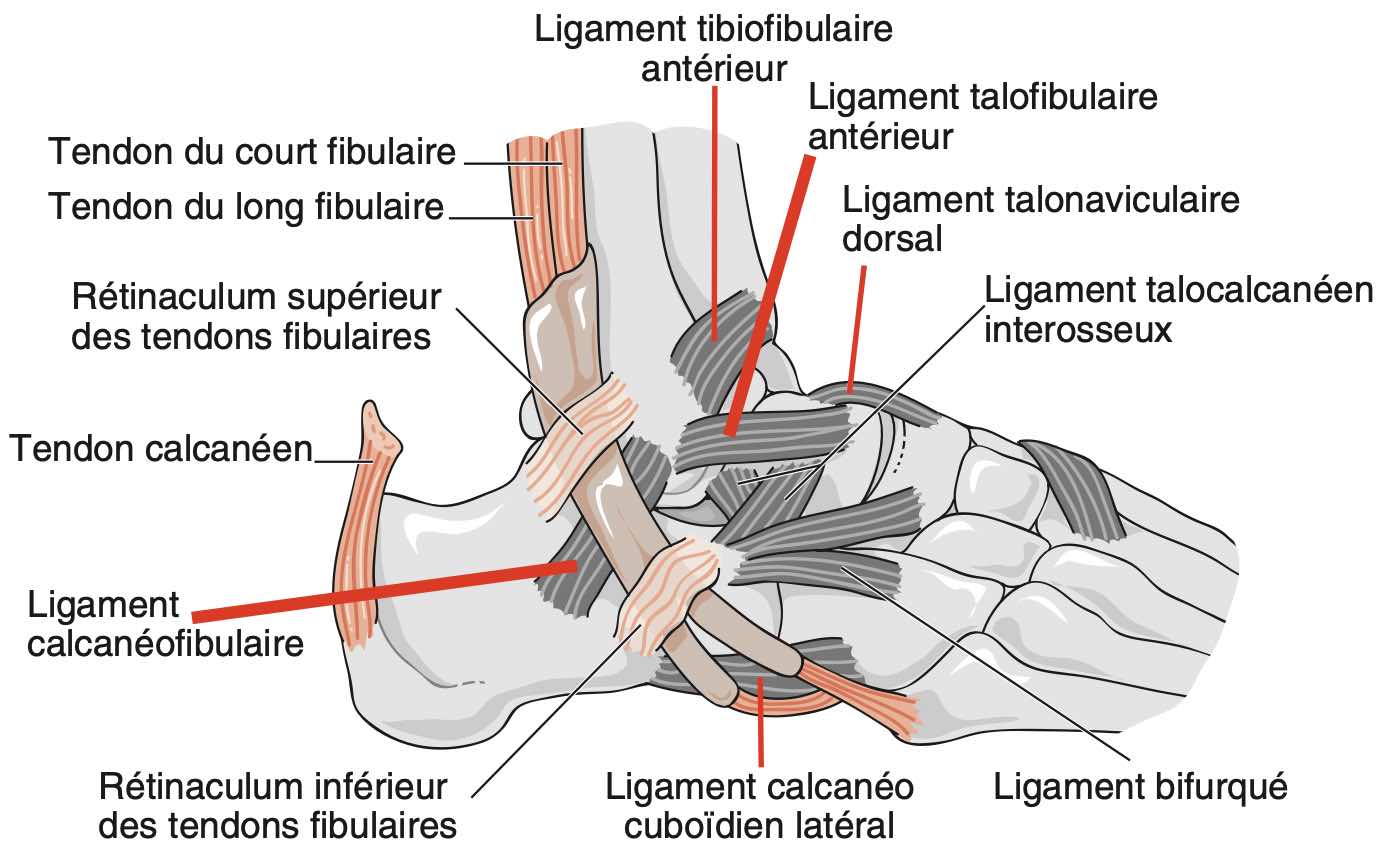

Entorse

Pas d'épanchement dans l'articulation tibio-talienne.

Aspect normal des ligaments talofibulaire antérieur et calcanéofibulaire.

Respect des ligaments talonaviculaire dorsale, tibiofibulaire antéro-inférieur et calcanéocuboïdien latéral.

Comblement graisseux hyperéchogène sans particularité du sinus du tarse.

Tendons court et long fibulaires en place, sans épanchement.